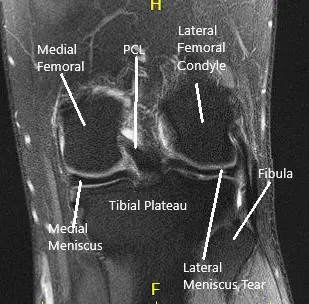

MRI of the left knee suggested a  lateral meniscal tear.. There was mild  partial-thickness cartilage loss along the central trochlear groove and in the lateral compartment.

MRI of the Knee in coronal and sagittal sections 2